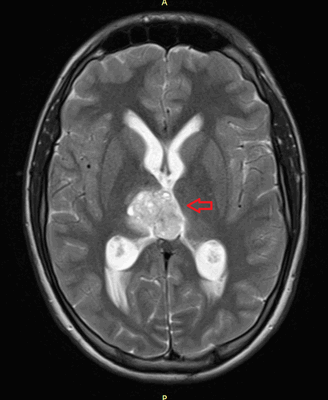

Также выполняют МРТ головного мозга, чтобы выявить наличие метастазов в нем.

![Метастаз в головной мозг при герминогенных опухолях (МРТ головного мозга)]()

Метастаз в головной мозг при герминогенных опухолях (МРТ головного мозга)

![Метастаз в головной мозг при герминогенной опухоли]()

Рисунок 9. – метастаз в головной мозг при герминогенной опухоли.